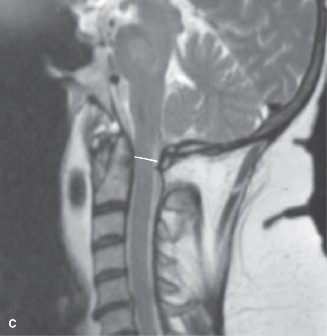

Pre-Operative Planning, Templating, and Patient Positioning

When surgical intervention becomes unavoidable, meticulous pre-operative planning is the cornerstone of a successful outcome. Advanced imaging is non-negotiable. An MRI with and without gadolinium contrast is the gold standard for defining the extent of the epidural abscess, the degree of neural compression, and the involvement of adjacent paraspinal musculature (e.g., psoas abscess). T1-weighted images typically show hypointense signals in the infected marrow, while T2-weighted and STIR sequences reveal hyperintense fluid and edema in the disc space and vertebral bodies. Gadolinium enhancement highlights the vascularized inflammatory phlegmon and the capsule of any abscesses.

In addition to MRI, a fine-cut computed tomography (CT) scan is essential for evaluating bony destruction. CT allows the surgeon to assess bone stock for pedicle screw purchase and to template the size of the interbody cages required for anterior column reconstruction. Upright standing radiographs (if the patient can tolerate them) or full-length supine films are necessary to evaluate global spinal alignment and regional kyphosis.